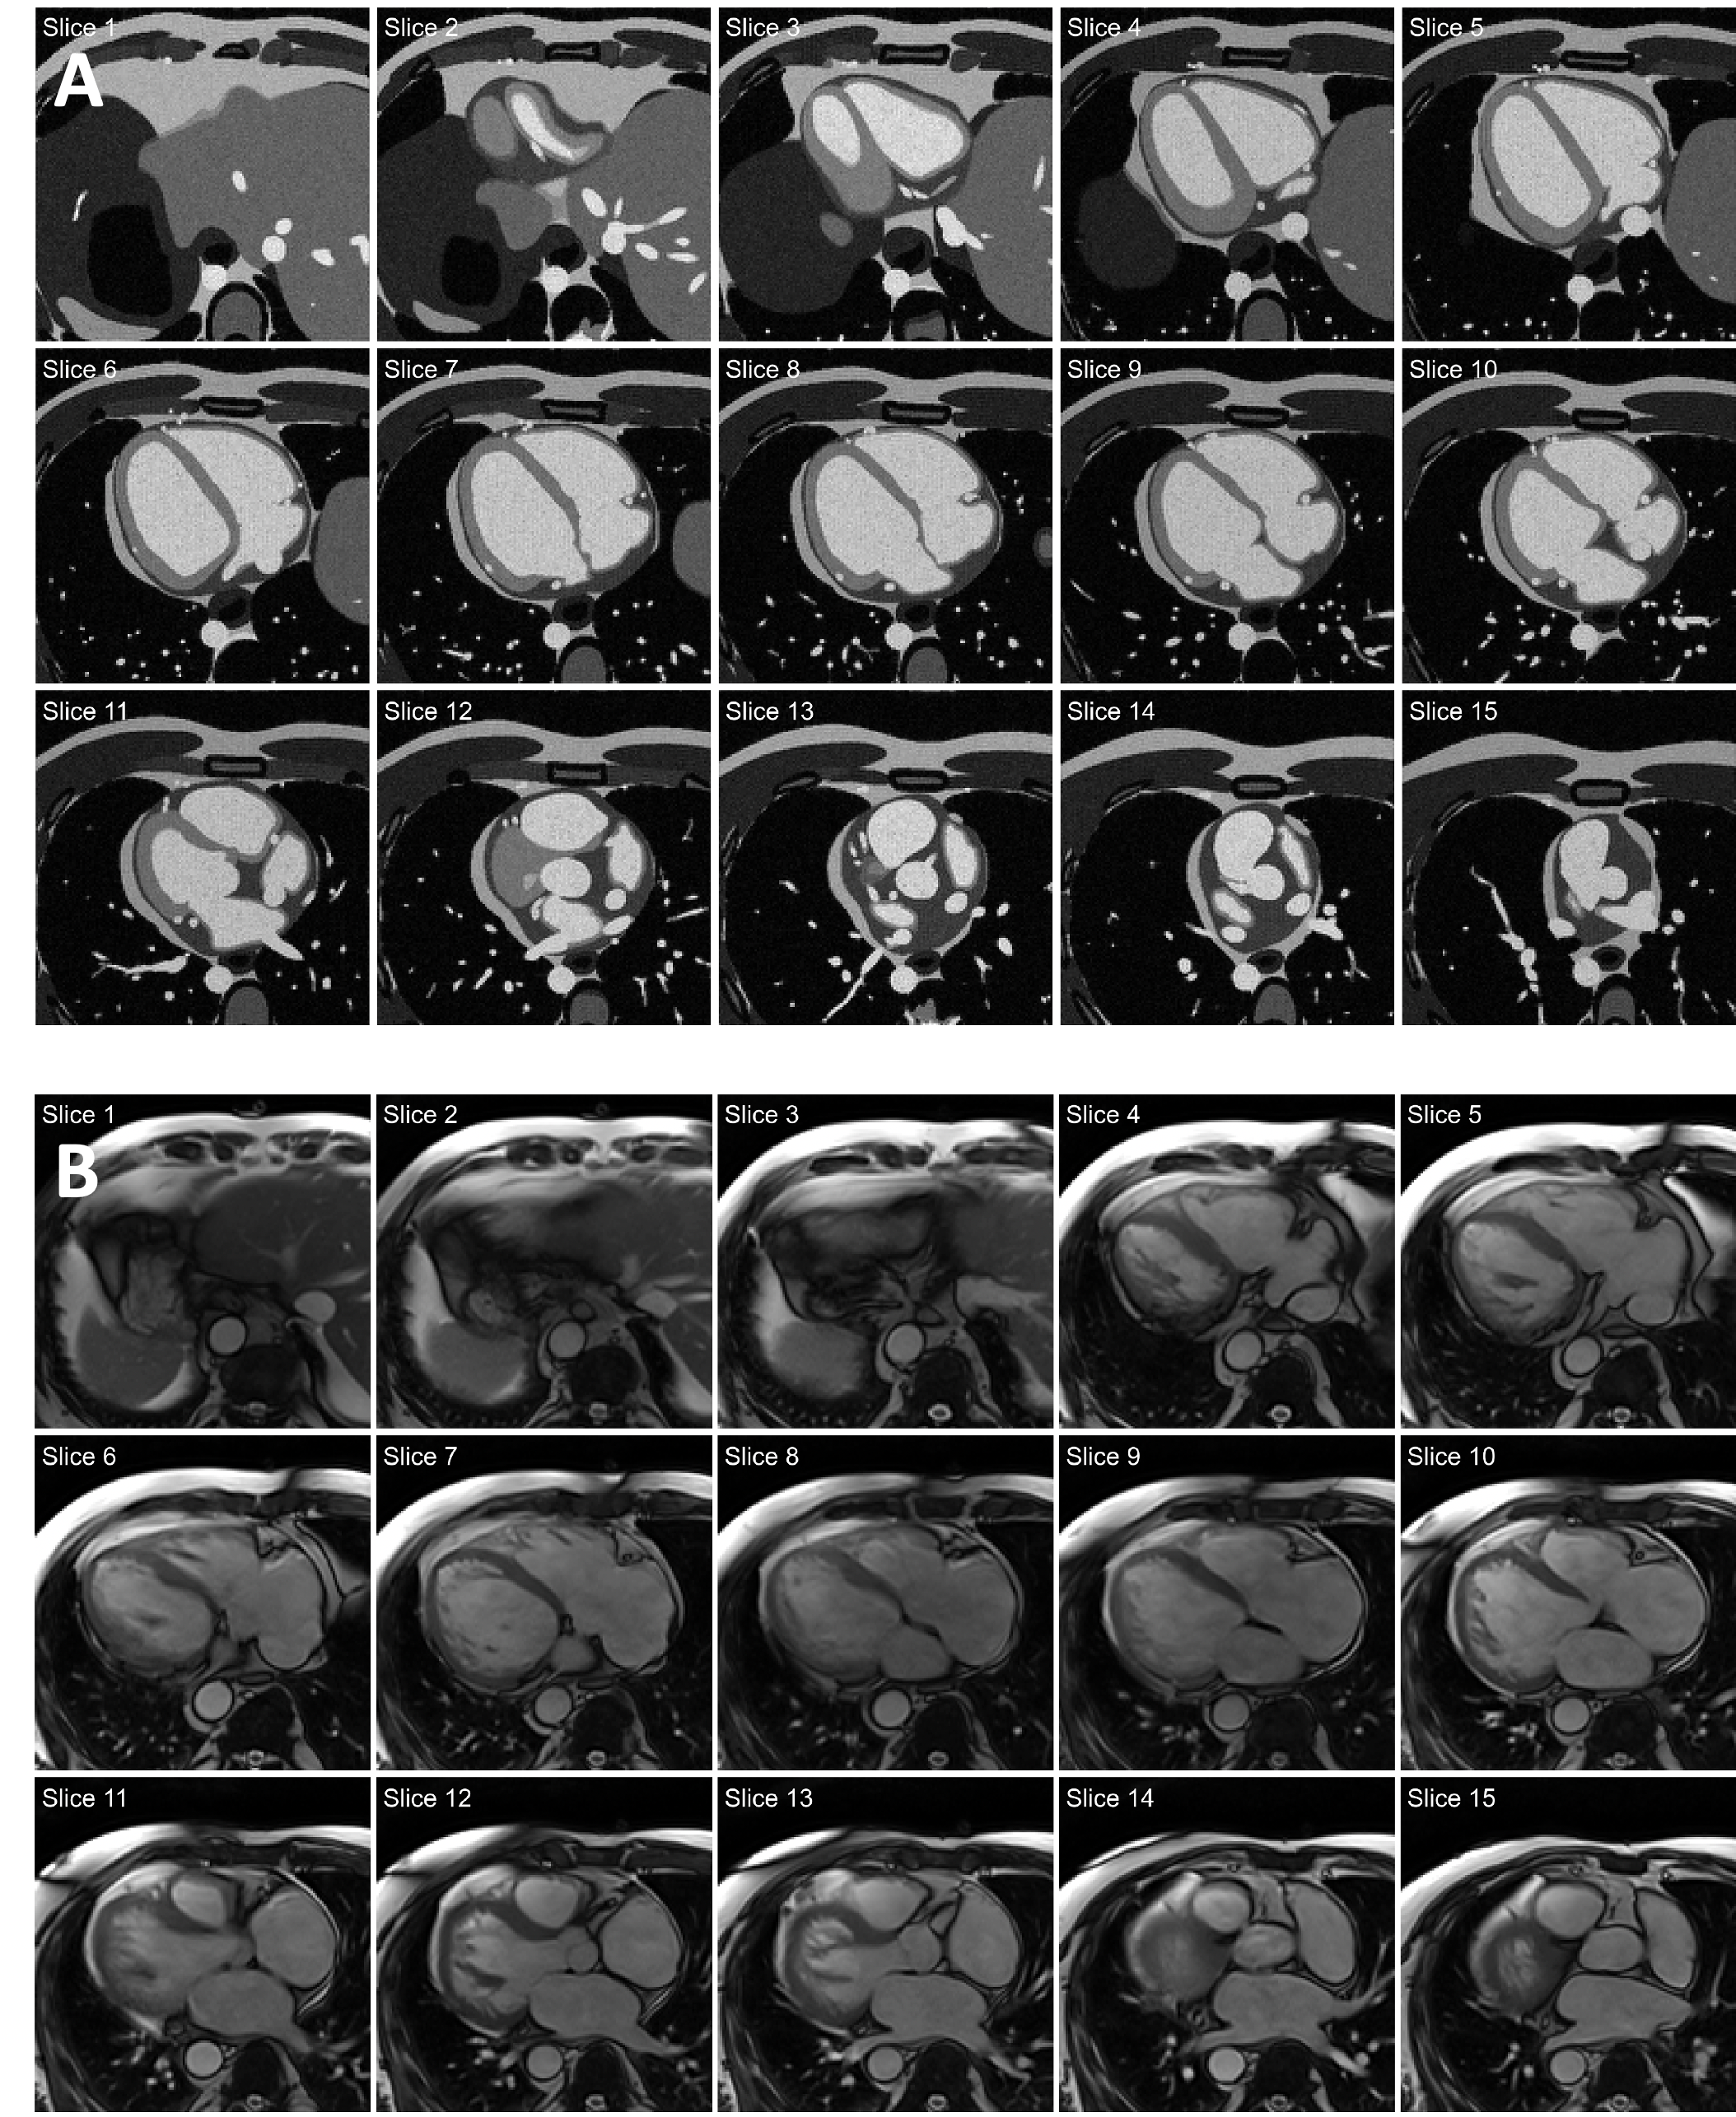

The simulator was able to generate realistic sets of cardiac MR images according to the visual assessment of experts. All represented anatomical structures preserved their smooth, non-overlapping boundaries. A representative example is shown in Fig 3A. The simulation of each 3D cardiac image took approximately 2 h on a single CPU. By distributing the image generation process across 64 CPUs, we were able to simulate sets of 500 cardiac MR images in less than 16 h. Despite differences in contrast and anatomy, the simulated images compare well with the cropped patient images depicted in Fig 3B, showing similar cardiac structures in an equivalent anatomical context.

Refer to caption

Figure 3: Examples of stacks of axial cardiac images. A: Images simulated using the proposed framework. B: Patient images acquired in a 1.5T scanner.